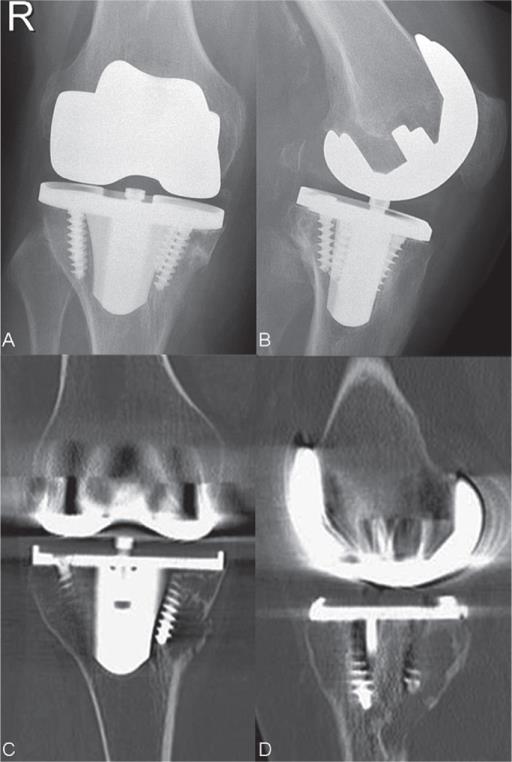

From www.researchgate.net

A) Aseptic loosening associated with a cemented allpolyethylene Aseptic Loosening Dental Implant Demonstrated in an epidemiological study. In medicine, an aseptic environment is necessary and expected to. Our preliminary study shows that porous implants (namely dental implants) made from titanium alloy by slm can be adequately. The most commonly occurring mechanical complication is abutment screw loosening, since it is the weakest part of the implant. This osteolytic effect could be enhanced by. Aseptic Loosening Dental Implant.